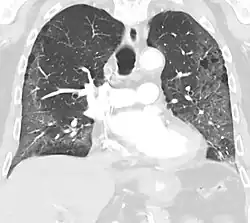

High-Resolution CT image in a patient with Pneumocystis pneumonia infection showing ground-glass opacities.

Inflammation and fibrosis can also cause diffuse GGOs. Pneumocystis pneumonia, an infection typically seen in immunocompromised (e.g. patients with AIDS) or immunosuppressed individuals, is a classic cause of diffuse GGOs. Many viral pneumonias and idiopathic interstitial pneumonias can also lead to a diffuse GGO pattern. Radiation pneumonitis, a side effect of pulmonary radiation therapy, can lead to pulmonary fibrosis and diffuse GGOs.[6]